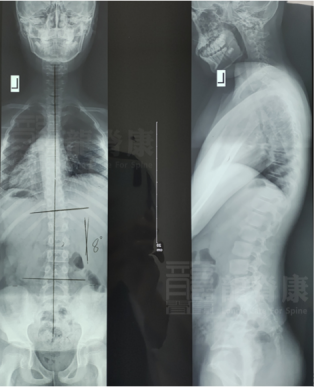

深圳龍脊康醫(yī)師部黃耿沛主任,在不久前,就接診了類似的案例,讓我們一起來看看他的分享:10歲男孩在半年前被發(fā)現(xiàn)高低肩、體態(tài)異常,于是家長(zhǎng)趕緊帶孩子到醫(yī)院拍片,確診脊柱側(cè)彎Cobb角約8°,生理曲度除了頸曲反弓的趨勢(shì)外,胸腰椎的曲度存在。

所以,黃耿沛主任給孩子定制了運(yùn)動(dòng)康復(fù)訓(xùn)練的治療。通過一次的訓(xùn)練后,從下圖中我們可以看出:訓(xùn)練前男生右肩高,左臀高,身體左后旋;訓(xùn)練后體態(tài)恢復(fù)正常。